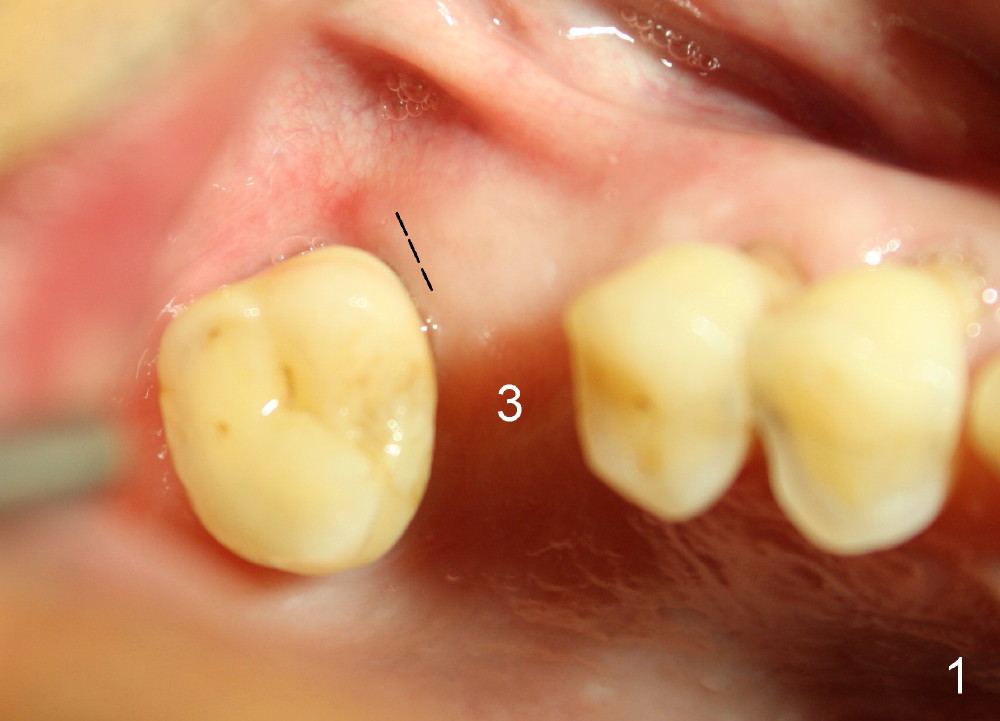

The implant is also found to have been placed buccal (Fig.6 B (CBCT 2 years 9 months post cementation)). In spite of one buccal thread exposure (Fig.8 I), there is no sign of periimplantitis 5 years 3 months post cementation, as related to good oral hygiene (Fig.7).